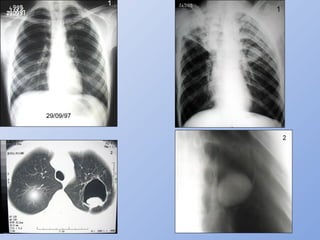

MICOSES PULMONARES

 RADIOLOGIA – ASPERGILOMARADIOLOGIA – ASPERGILOMA